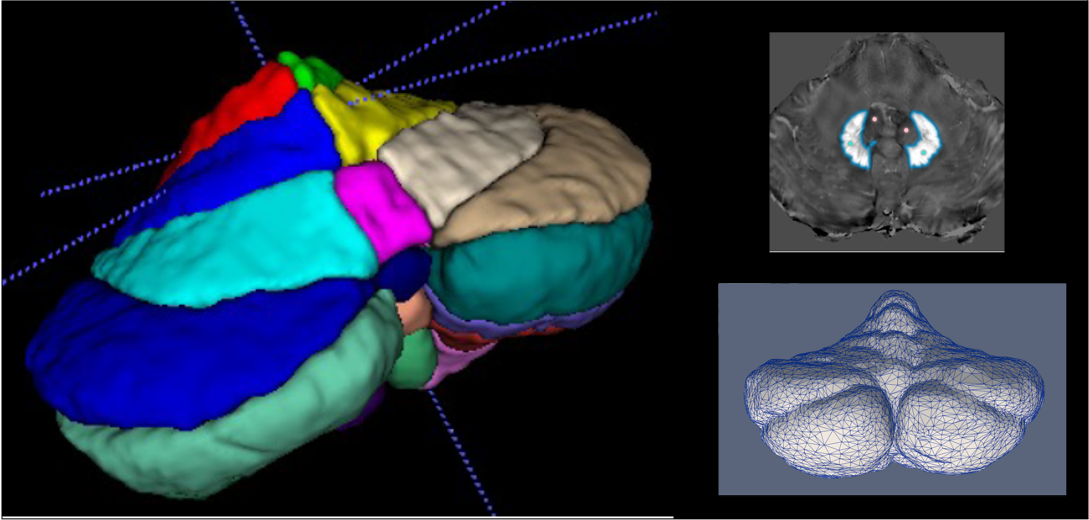

Automated Segmentations & AI-driven MRI Analysis

Leveraging cutting-edge artificial intelligence (AI) methods, we analyze MRI images to identify disease specific alterations. We have successfully implemented CerebNet, a fast and reliable deep-learning pipeline for detailed cerebellum sub-segmentation with high anatomical accuracy (Code on Github). Further development of CerebNet is underway, with extensions for sub-segmentation of high-resolution MRI and inclusion of the brainstem and cerebellar peduncles. Moreover, we are implementing segment anything pipelines as well as unsupervised surface analyses. Our objective is to enhance our understanding of disease related structural changes. By discerning subtle changes in the brain, we aim to contribute valuable insights that may not only deepen our comprehension of the disease but also foster the development of novel treatments by informing the design of clinical trials.